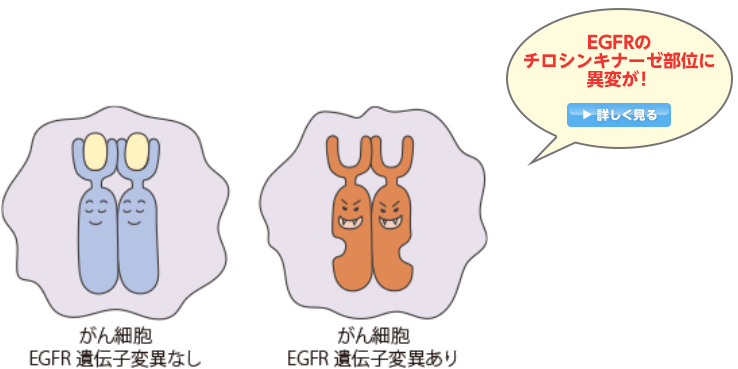

日本人に多いEGFR遺伝子変異とは?

日本人に多いEGFR遺伝子変異

非小細胞肺がんの細胞の表面にはEGFR(上皮成長因子受容体)と呼ばれるタンパク質がたくさん発現しており、このEGFRは、外部から刺激を受けると、がん細胞が増え続ける(増殖)のに必要な信号を細胞内に伝える役割を担っています。

非小細胞肺がんにはこのEGFRを構成している遺伝子の一部(チロシンキナーゼ部位)に変異が認められる腫瘍があることがわかっています。

変異の中にはEGFRのスイッチを常時ONにして、がん細胞の増殖を促すものもあります。

EGFR遺伝子変異は、日本人の非小細胞肺がんの患者さん全体の30〜40%に認められます。欧米人よりも日本人などのアジア系の人種、男性よりも女性、タバコを吸う人よりも吸わない人に多く、非小細胞肺がんの中でも腺がんの患者さんに多いことなどがわかっています。

遺伝子変異とは、遺伝子(DNA)を作っている塩基(アデニン(A)、グアニン(G)、チミン(T)、シトシン(C)の並び方が正常な場合とは異なっている状態のことです。

EGFR遺伝子変異には、いくつかのパターンがあります。特に発現が多い遺伝子変異は、EGFR遺伝子の中のエクソン19という部位の一部がなくなっている「エクソン19欠失」、エクソン21という部位の塩基の並びが入れ替わっている「L858R点変異」です。

また、たばこを吸う人はEGFR遺伝子変異が認められる割合が低い傾向がありますが、腺がんであれば喫煙者の約30%に変異が認められます。

こうしたことから、性別、喫煙歴、がんの種類(腺がん・非腺がん)などの患者背景に関係なくEGFR遺伝子変異検査の実施が勧められます。

肺がんの治療薬であるEGFRチロシンキナーゼ阻害薬(EGFR-TKI)は、EGFR遺伝子変異のある患者さんで効果の高い薬剤といわれています。また、非小細胞肺がんの扁平上皮がんでは、EGFR遺伝子変異の発現頻度がとても低いことがわかっています。このため、扁平上皮がん以外の組織型の非小細胞肺がん患者さんは、薬物療法を開始する前にEGFR遺伝子変異検査をおこない、陽性の場合にEGFR-TKIを使うことが推奨されています。